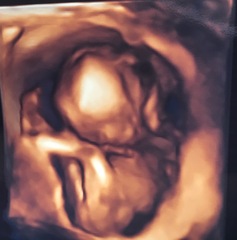

rhodes2015 · 09/03/2017 21:00

Butterfly this is our 4d scan at 16+4 private gender scan. Can't make out face but can see her curled up and foot is clear.

And then 23+2 today just her face and hands (nhs)

The pictures aren't amazingly clear as consultant was trying to get a picture without the cord in the way or her hand over her face but live was brilliant to watch and could see her opening and closing her mouth very clear.

I read on the private scanning centre website near us that 27 or 28 weeks gives the best view on 4d of face.